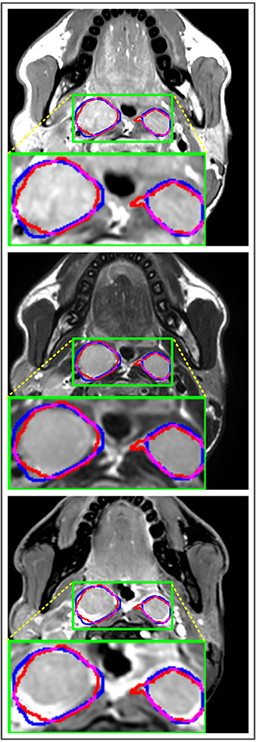

Refer to caption

(a) DSC=0.915

(b) DSC=0.870

(c) DSC=0.902

(d) DSC=0.898

Figure 7: Predicted results of proposed MMFNet in 2D images. There are corresponding T1, T2 and CET1 images from top to down. Boundaries created by radiologists are marked in red line, and the predicted boundaries are shown in blue line. The DSC𝐷𝑆𝐶DSC value is the dice similarity coefficient of this single slice.

Comparison with ground truth. Some predicted results of MMFNet are shown in 2D images and 3D images in Figure 7 and Figure 8. As shown in these figures, although the shape and size of NPC are varied from each other, MMFNet can still accurately determine the regions of NPC and obtain the accurate contours of tumors. Through analyzing 2D images in figure 7, MMFNet has a capacity to fuse multi-modality MRI to reduce the confusion brought by intensity’ similarity between nearby tissues and NPC. The values of meanDSC𝑚𝑒𝑎𝑛𝐷𝑆𝐶meanDSC, meanASD𝑚𝑒𝑎𝑛𝐴𝑆𝐷meanASD and meanHD𝑚𝑒𝑎𝑛𝐻𝐷meanHD of MMFNet are shown in Table 1. MMFNet can reach the best results with DSC=72.38%,meanASD=2.07mmformulae-sequence𝐷𝑆𝐶percent72.38𝑚𝑒𝑎𝑛𝐴𝑆𝐷2.07𝑚𝑚DSC=72.38\%,meanASD=2.07mm, and meanHD=18.31mm𝑚𝑒𝑎𝑛𝐻𝐷18.31𝑚𝑚meanHD=18.31mm.